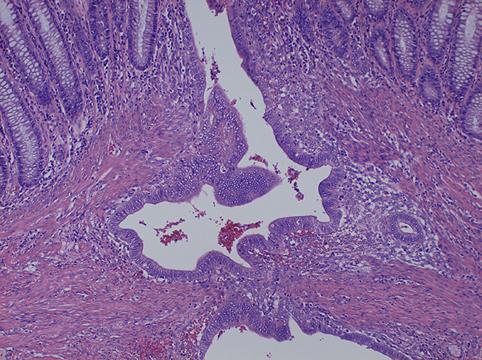

疾患(病理主体)の分類腫瘍様病変/子宮内膜症

部位(臓器別)大腸/S状

検査方法ミクロ

病変の最大径(ミリ)40以上